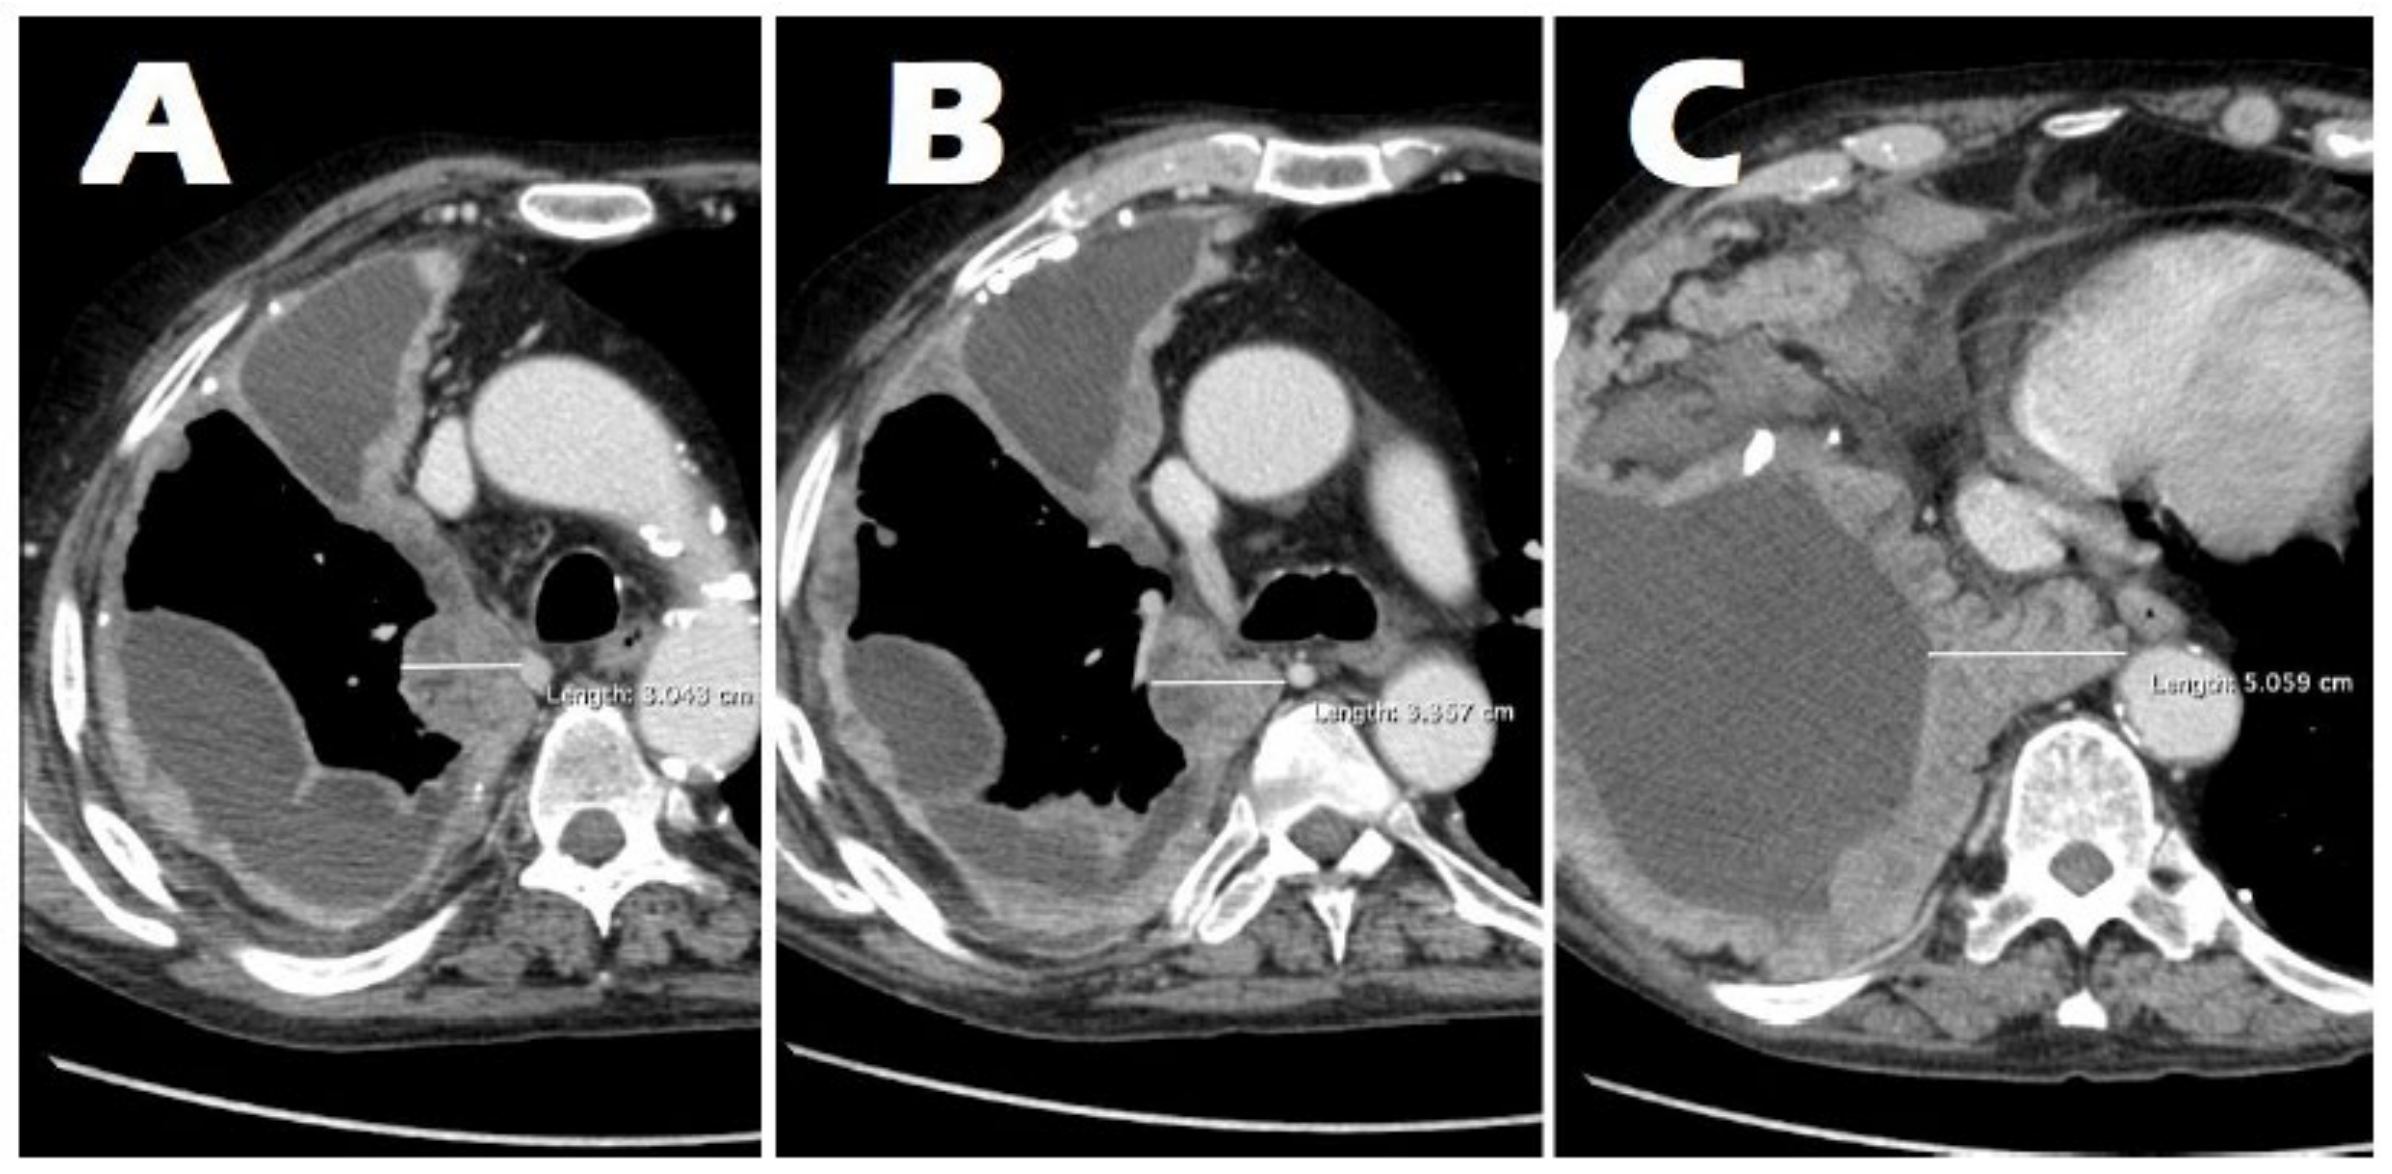

3.2. Radiological Findings on Chest CT

3.3. Correlation Between Tumor Thickness and the T Parameter

3.4. Correlation of Tumor Volume with Tumor Thickness and the T Parameter

| Average tumor thickness (median [range]), mm | 12.4 [7.9–17.9] |

| Maximum tumor thickness (median [range]), mm | 18.3 [10.8–26.3] |

| Tumor volume (median [range]), mL | 27.7 [15.7–88.1] |

| Pleural effusion volume (median [range]), mL | 1784.1 [821.6–2697.0] |